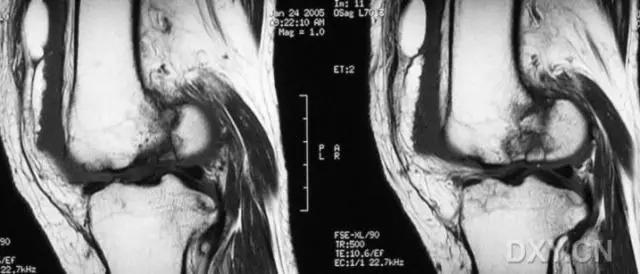

6. Pipkin 骨折

股骨头骨折。1957 年,Pipkin G 在文献中对其进行详细的描述并分型,至今仍在很多文献中被采用。

(来源:radiopaedia)

-

Ⅰ型:骨折块在圆韧带的下方;

Ⅱ型:骨折块在圆韧带的上方;

Ⅲ型:Ⅰ、Ⅱ两型任意一种伴股骨颈骨折;

Ⅳ型:Ⅰ、Ⅱ两型任意一种伴髋臼骨折 。